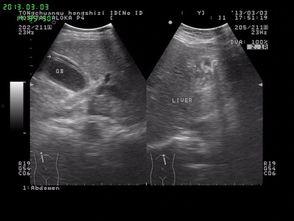

接下来,让我们一起来了解一下蛔虫手术的具体过程。首先,医生会为患者进行全身麻醉,确保患者在手术过程中不会感到疼痛。医生会在患者的腹部切开一个小口,找到寄生着蛔虫的肠道。接着,医生会小心翼翼地将蛔虫从肠道中取出,最后缝合伤口。